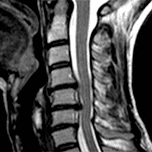

我們是一家位於西班牙巴塞隆納的國際專科醫療中心,不設分院,專注於精準且高品質的醫療照護。我們採用微創手術從病因治療Arnold-Chiari I型症候群、特發性脊髓空洞症與脊柱側彎等相關疾病,致力於為來自世界各地的患者帶來更安全、更有效的治療選擇。